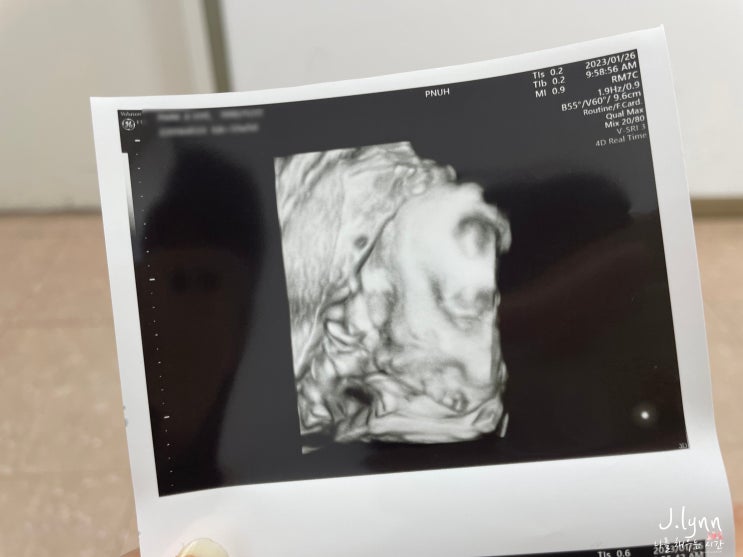

[임신기록 22] - 임신35-36주 막달증상 막달검사 태동검사 아기용품세탁

임신기록 22 임신35-36주 막달증상 막달검사 태동검사 아기용품준비 - 임신35주 막달증상 - #임신35주 #막...